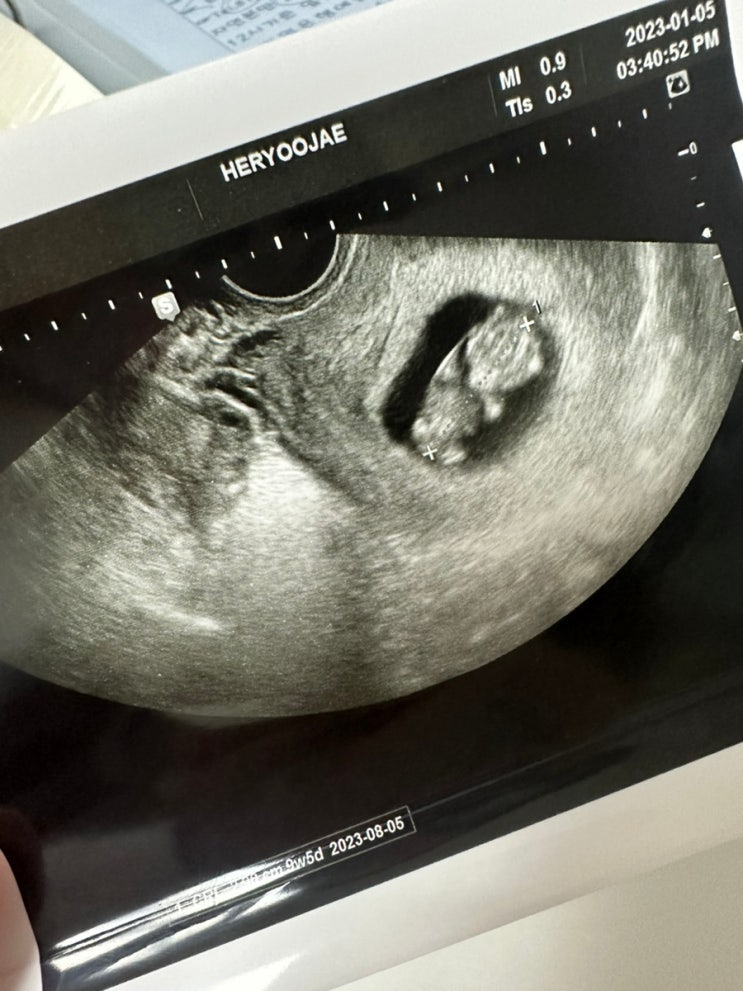

임신 9주5일 젤리곰이 움직이다?!

2023.01.05 목요일 나는 월차 남편은 오후반차 병원예약은 16:40 남편 퇴근시간맞춰서 나왔다 은행업무 본...